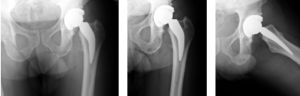

Case Report #4

Scott Dunitz, MD

Tulsa Bone and Joint Associates

A 59-year-old Caucasian male weighing 192lbs diagnosed with osteo/degenerative arthritis received Advita’s Alteon Neck Preserving stem with a Bioloxdelta femoral head and InteGrip acetabular shell. The patient went under spinal anesthesia using a direct anterior surgical approach with an incision size of 9cm. There was an estimated blood loss of 200cc, and surgery duration was 63 minutes. The patient was discharged after one day postoperative with a walker to in home care for rehabilitation.

Pre-Op AP Pelvis

Harris Hip Score 60 (max=100) | Oxford Hip Score 25 (max=48)

6-Week Post-Op

Harris Hip Score 96 (max=100) | Oxford Hip Score 42 (max=48)

3-Month Post-Op

Harris Hip Score 96 (max=100) | Oxford Hip Score 37 (max=48)

1-Year Post-Op

Harris Hip Score 97 (max=100) | Oxford Hip Score 44 (max=48)

CONCLUSION

Previous to his total hip replacement, this patient presented with low Harris Hip and Oxford Hip scores. The outcomes of this case continue to be followed annually, and this patient is satisfied with his hip replacement. One year after his surgery, his scores increased by more than 38.1 percent on the Harris Hip and 43.2 percent on the Oxford Hip. The direct anterior approach used in this surgery has been associated with faster functional recovery than the posterolateral approach. •

Radiographs are captured and evaluated by an independent reviewer.